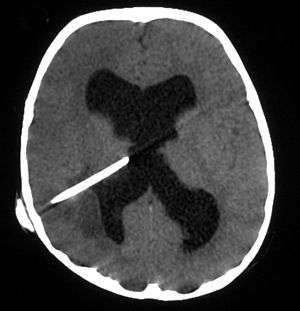

Bacterial abscesses rarely (if ever) arise de novo within the brain, although establishing a cause can be difficult in many cases. There is almost always a primary lesion elsewhere in the body that must be sought assiduously, because failure to treat the primary lesion will result in relapse. In cases of trauma, for example in compound skull fractures where fragments of bone are pushed into the substance of the brain, the cause of the abscess is obvious. Similarly, bullets and other foreign bodies may become sources of infection if left in place. The location of the primary lesion may be suggested by the location of the abscess: infections of the middle ear result in lesions in the middle and posterior cranial fossae;[5] congenital heart disease with right-to-left shunts often result in abscesses in the distribution of the middle cerebral artery;[6][7] and infection of the frontal and ethmoid sinuses usually results in collection in the subdural sinuses.

The diagnosis is established by a computed tomography (CT) (with contrast) examination. At the initial phase of the inflammation (which is referred to as cerebritis), the immature lesion does not have a capsule and it may be difficult to distinguish it from other space-occupying lesions or infarcts of the brain. Within 4–5 days the inflammation and the concomitant dead brain tissue are surrounded with a capsule, which gives the lesion the famous ring-enhancing lesion appearance on CT examination with contrast (since intravenously applied contrast material can not pass through the capsule, it is collected around the lesion and looks as a ring surrounding the relatively dark lesion). Lumbar puncture procedure, which is performed in many infectious disorders of the central nervous system is contraindicated in this condition (as it is in all space-occupying lesions of the brain) because removing a certain portion of the cerebrospinal fluid may alter the concrete intracranial pressure balances and causes the brain tissue to move across structures within the skull (brain herniation).

Surgical drainage of the abscess remains part of the standard management of bacterial brain abscesses. The location and treatment of the primary lesion also crucial, as is the removal of any foreign material (bone, dirt, bullets, and so forth).